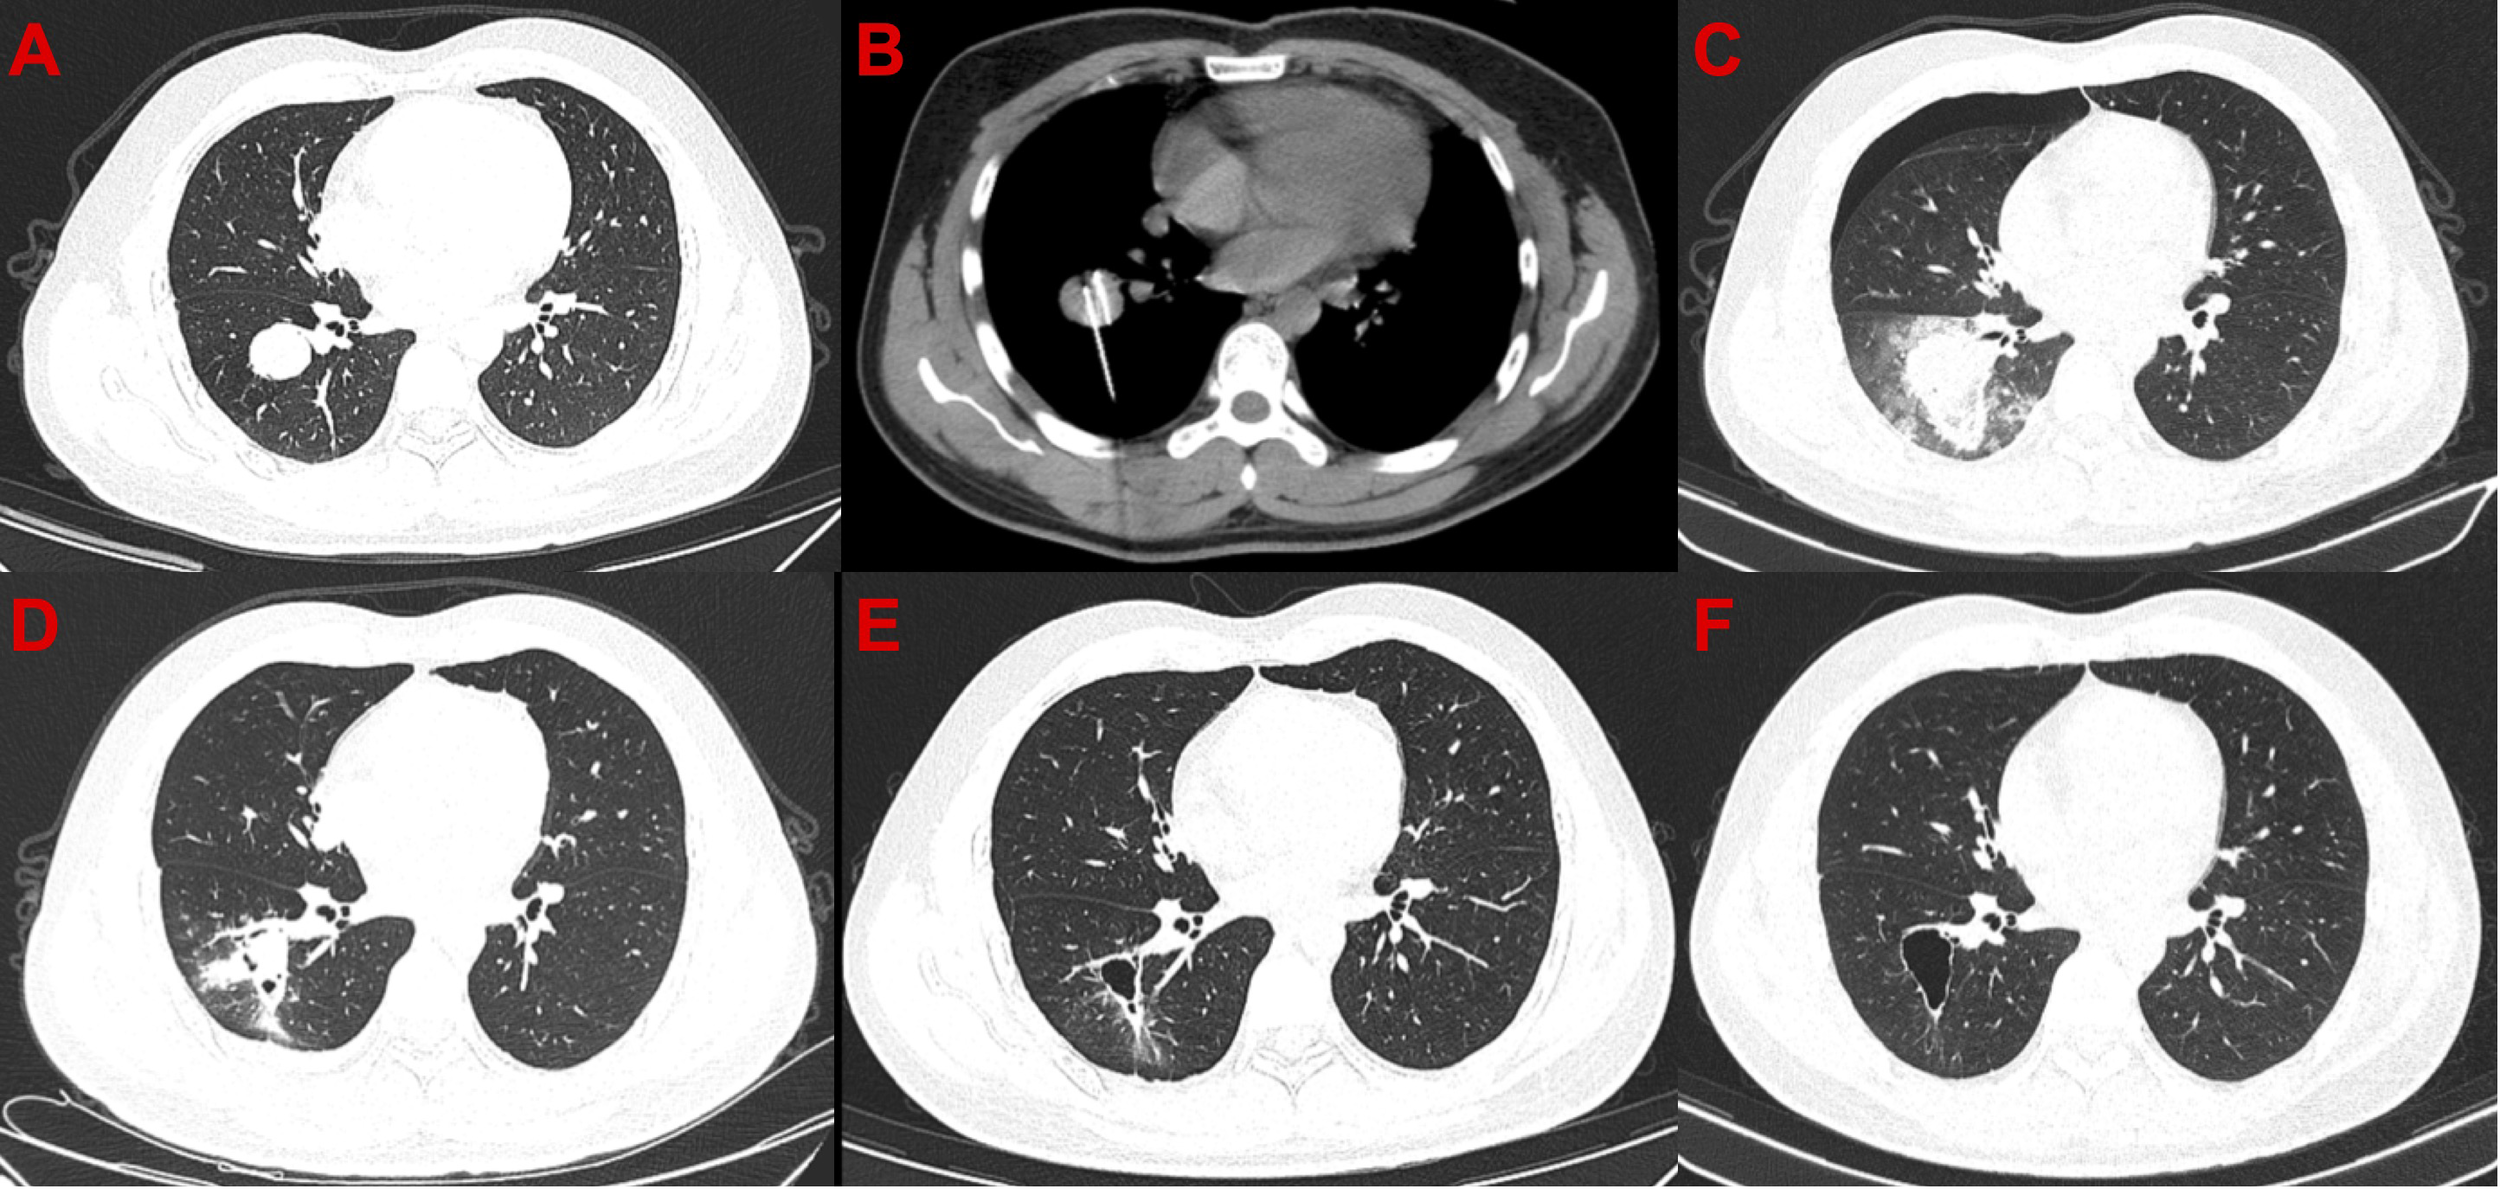

Figure 2

Computed tomography images of the only patient with complete response after cryoablation. (A) Before cryoablation. (B) During cryoablation. (C) After cryoablation, local large-scale inflammation and pneumothorax can be observed. (D) One month after cryoablation, pneumothorax disappeared, and the scope of inflammation narrowed. (E) Moreover, 3.5 months after cryoablation, cavity formation was observed in the diseased area. (F) 7.5 months after cryoablation.

In this study, 27 patients with STS were received argon-helium knife cryoablation plus PD-1 inhibitor treatment. The results showed that 96.3% (26/27) of the patients experienced the control of the size of target lesions. This suggests that cryoablation is effective in treating STS metastases. However, only 7.4% (2/27) of the patients receiving cryoablation showed a reduction in the diameter of distant lesions. This suggests that cryoablation combined with PD-1 inhibitor treatment is hard to produce synergistic effects as it does in other cancers (26, 27). There are many factors affecting the efficacy of PD-1 inhibitor. First, it may be due to the immune inertia of the sarcoma itself that the local increase in immunogenicity produced by cryoablation is insufficient to activate the body’s systemic antitumor immune response. Second, cryoablation inevitably leads to local bleeding, necrosis, and inflammatory reaction (Figures 2, 3). Nevertheless, the inflammatory response inhibits the efficacy of PD-1 inhibitor (28). Therefore, the effect of cryoablation on antitumor immune response is two-sided. It may improve antitumor immune response by improving immunogenicity or inhibit antitumor immune response by triggering inflammatory response. A study that found that the freezing rate of cryoablation had a significantly different effect on the immune system may confirm our conjecture (29). Third, adjuvant medication has an important effect. A prior study confirmed that the use of concomitant drugs (steroids, systemic antibiotics, proton pump inhibitors) was associated with worse clinical outcomes when receiving PD-1 inhibitor (30). In this study, we used the abovementioned adjuvant therapy agents in almost every patient. In addition, the combination sequence of cryoablation with PD-1 inhibitors may also be important. A current study has demonstrated that different sequences of chemotherapy combined with PD-1 inhibitors have significantly different effects on efficacy (31). In this study, all patients were treated with PD-1 inhibitor before cryoablation. This combination sequence may not be conducive to synergistic efficacy. A systematic follow-up study for a valid comparison of PD-1 inhibitor treatment before and after cryoablation can demonstrate which strategy could be clinically beneficial. In conclusion, there are many factors that lead to the lack of synergistic effect between cryoablation and PD-1 inhibitors in this study, and further studies are required. Additionally, it is worth noting that some studies have demonstrated that thermal ablation can promote the release of tumor antigens, thereby driving downstream immune responses (32–34). The differences in the effects of different ablation methods such as thermal ablation or cryoablation on anti-tumor immunity are also worth further research.

In general, cryoablation combined with PD-1 inhibitor has a safety profile, with rare serious complications. The most common complications are pneumonia and pleural effusion after treatment of lung lesions (Figures 2, 3). Patients with these complications are often treated with adjuvant medications, such as steroid hormones or antibiotics. Such adjunctive agents inhibit the antitumor immune response and even lead to a poor prognosis (30). This may be one reason for the absence of synergistic results in this study. Therefore, PD-1 inhibitor should not be considered in patients considering lung cryoablation until steroid hormones or antibiotics are confirmed to be unnecessary.